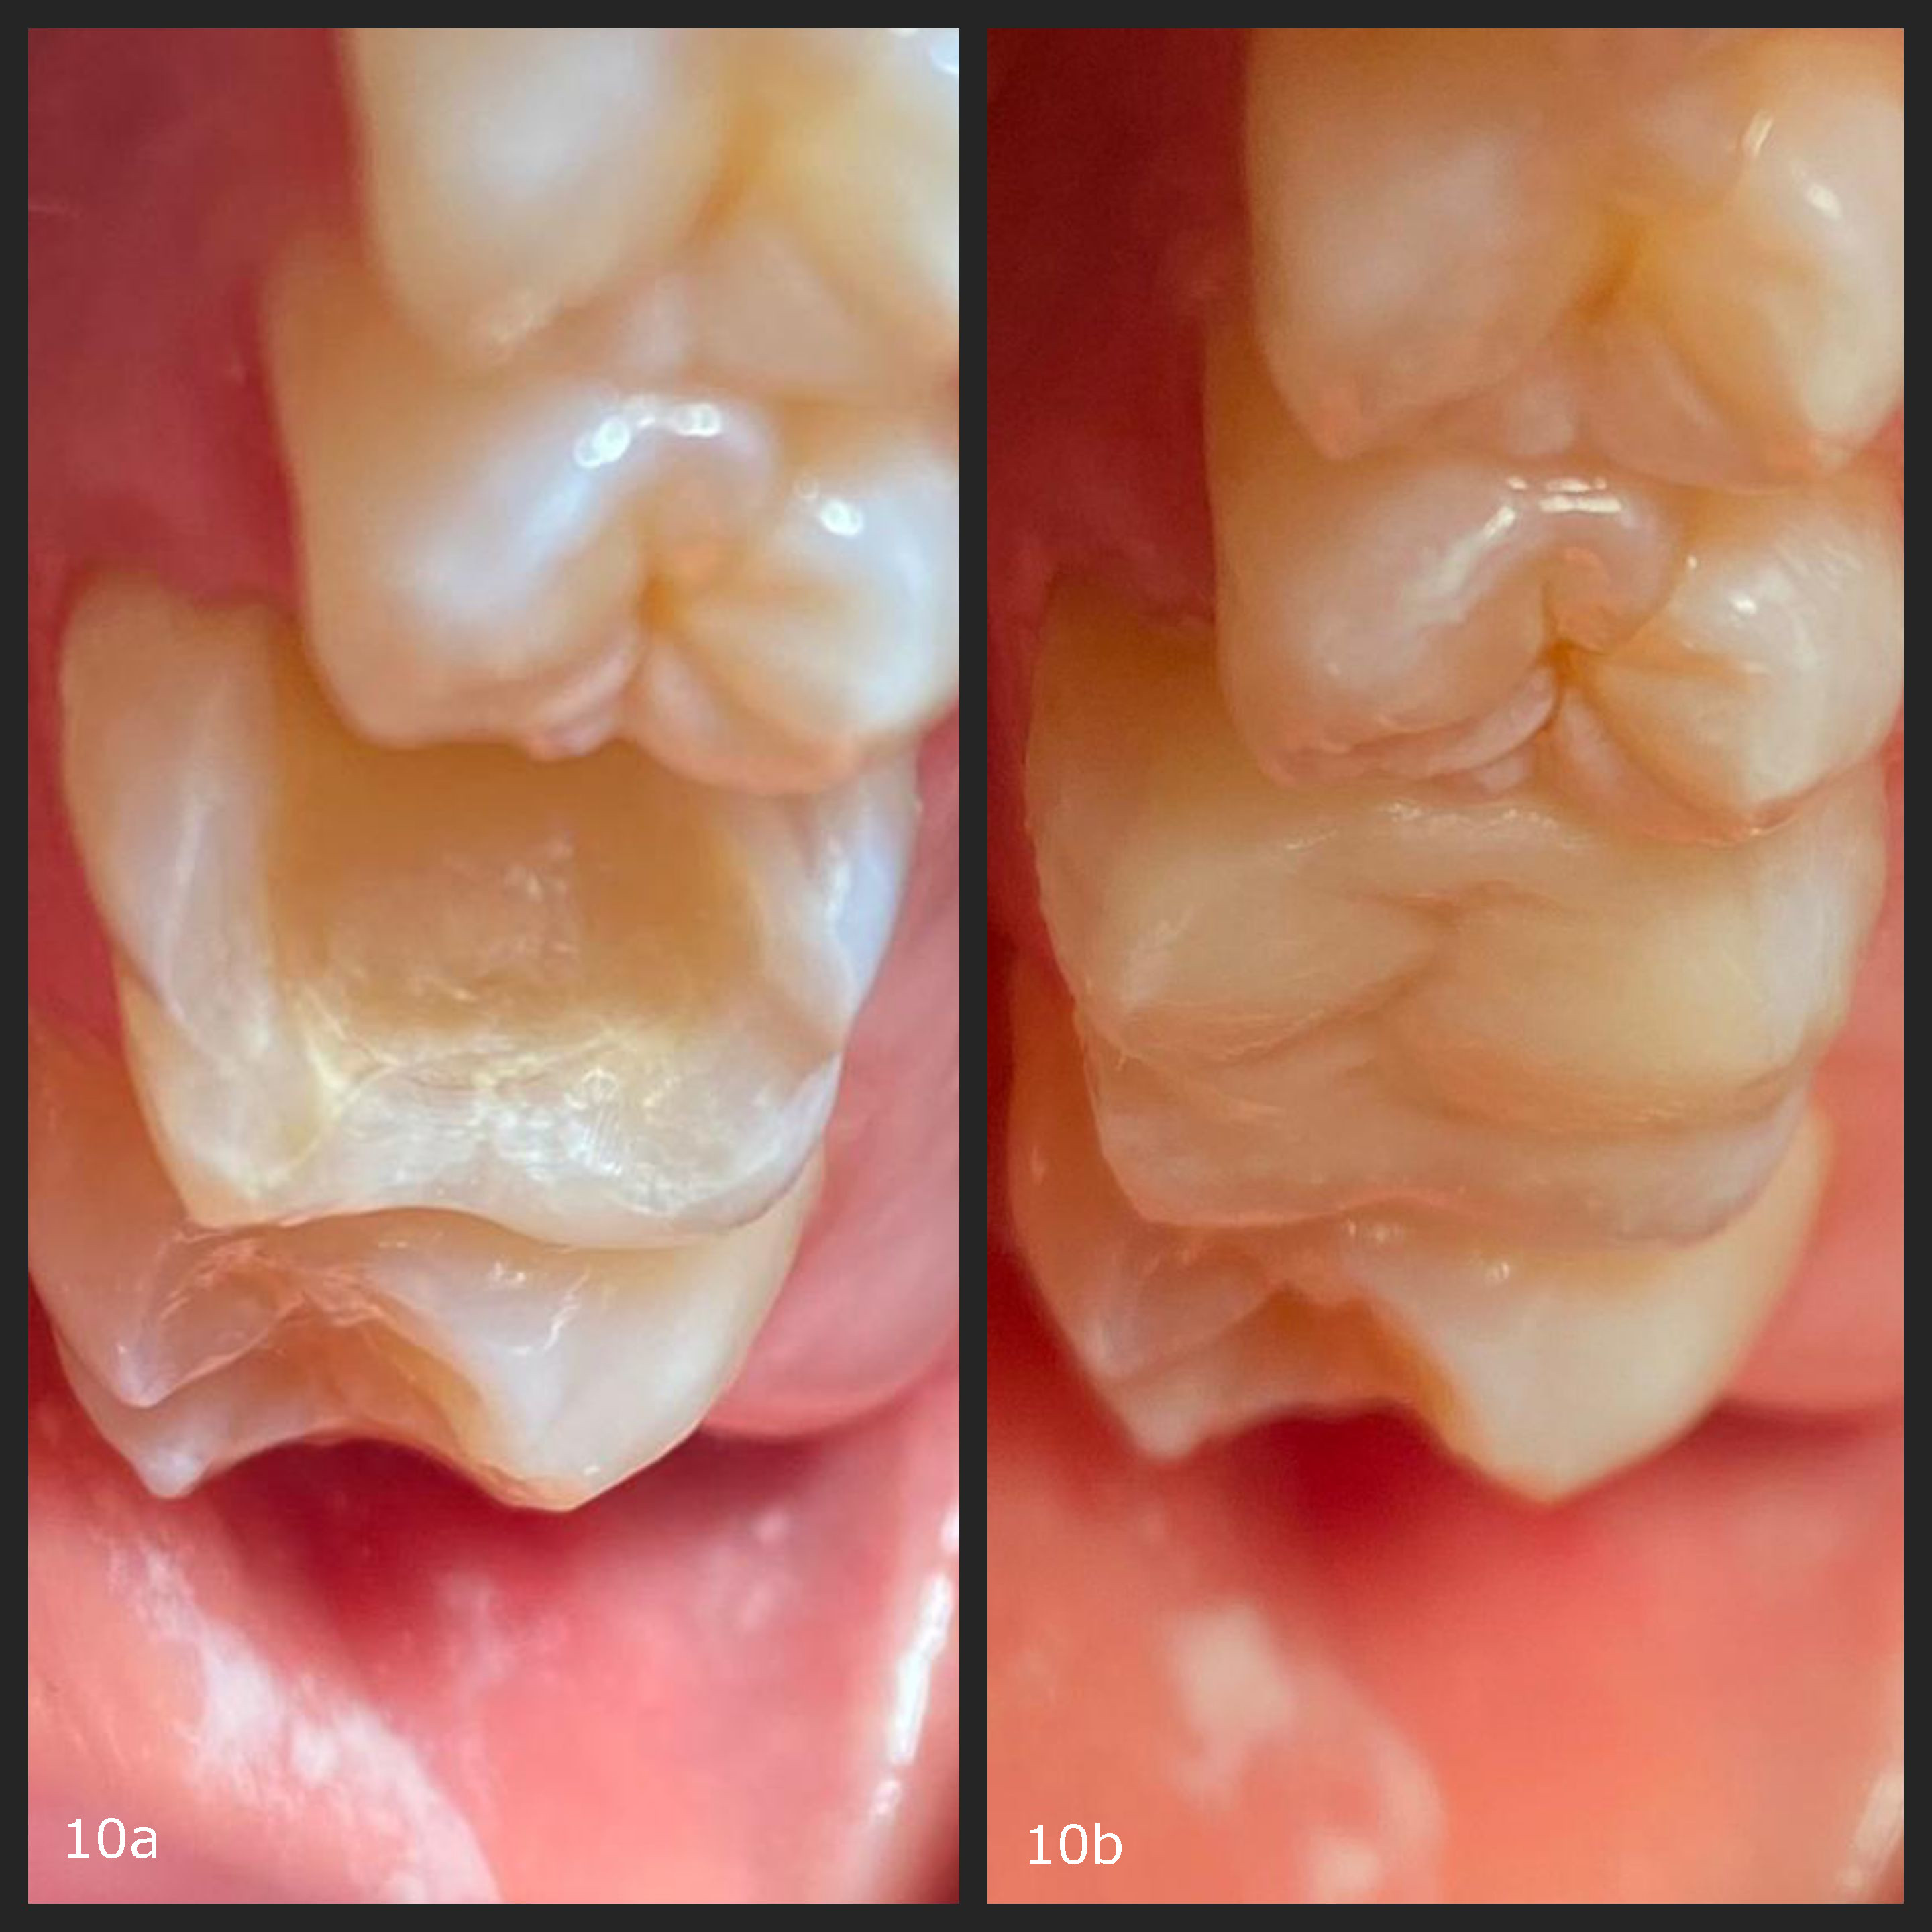

Fig. 10

Internal studies and clinical reports have demonstrated satisfactory clinical performance of both resins for periods of up to 18–24 months, particularly in single-unit cases. Semi-annual follow-up, occlusal verification and monitoring of functional wear are recommended. In the case of veneers, aesthetic outcomes have been shown to remain stable even at thicknesses of 0.3 mm (Fig. 10).